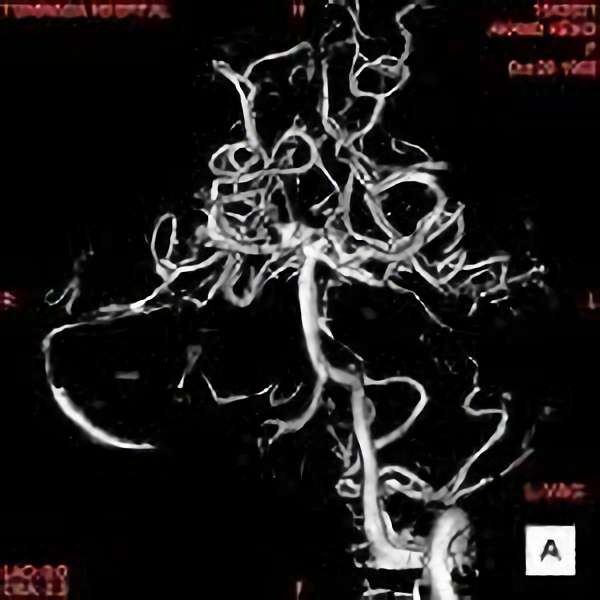

手術後

脳血管撮影により完全除去が確認された